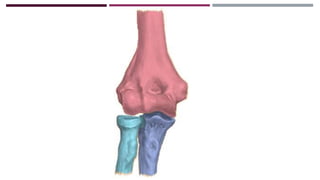

ANATOMÍA